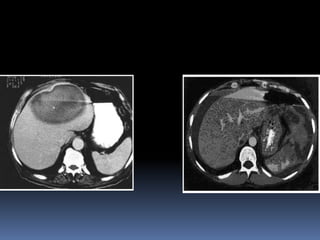

HIGADO: Más lesionado en

un trauma.

Con hallazgos

físicos mínimos.

Aún con cantidades

de sangre libre en

la cavidad .

• Apareciendo imágenes

heterogéneas, hiper o

hipoecogénicas,

compatibles con diversas

lesiones hepáticas.

ECOGRAFIA

• Más sensible para el

diagnóstico.TAC

Medicina Intensiva. Dr. Carlos Lovesio.

ATLS